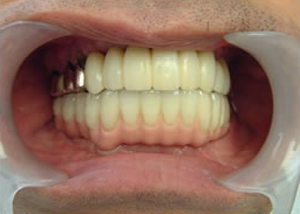

16.上は仕上がりが入り、下は仮歯です。

開口器を入れた口元

治療完了

平成21年1月29日

(治療期間:1年7ヶ月)